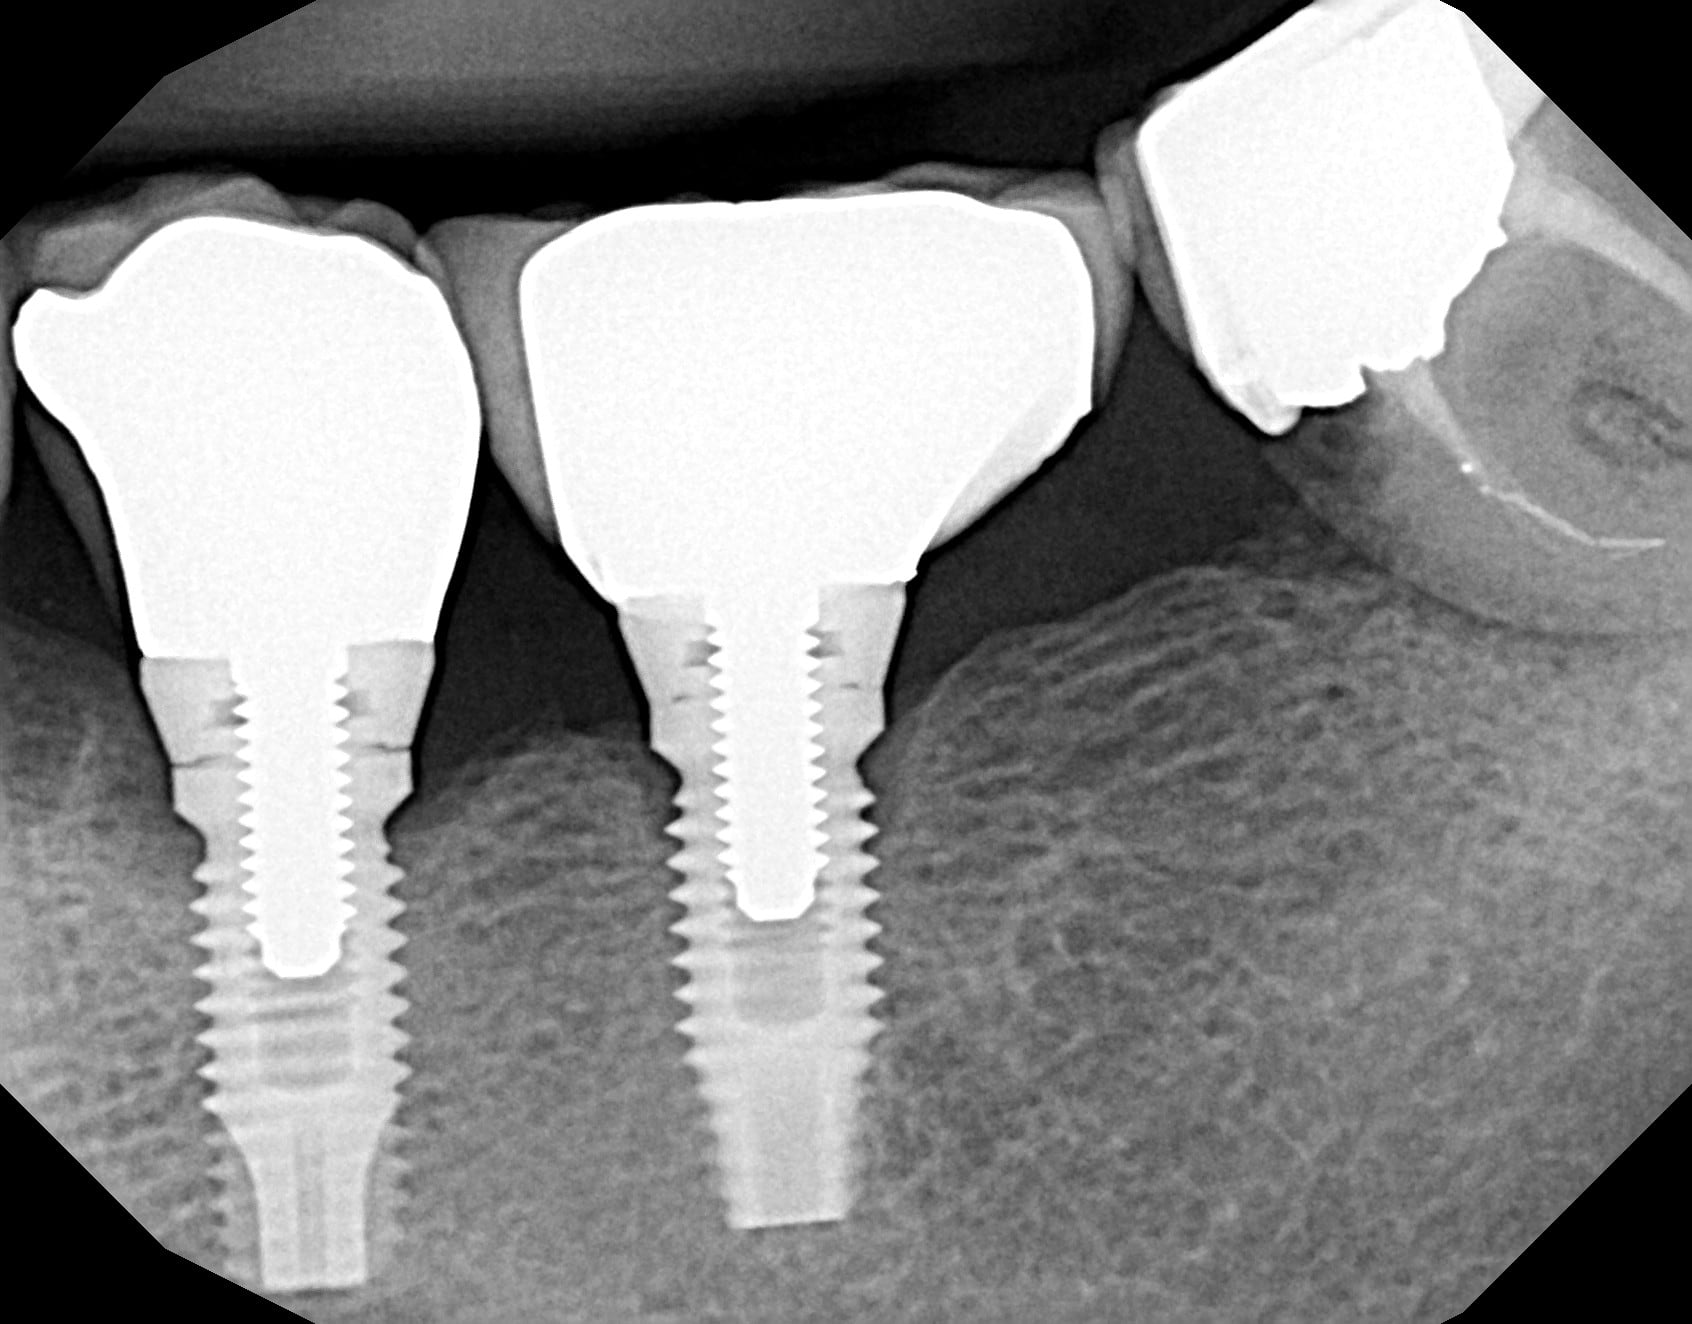

Bonjour, je recherche la référence de l'implant posé en 35 sur la radio ci-jointe.

Implant posé dans le 92 il y a au moins 15 ans, praticien en retraite depuis.

Nobel Branemark MKII

La vis en or (plus radio opaque) donne la bonne information : il n’y a plus que 3i qui en utilise…..et les encoches à l’apex sont différentes sur le Nobel….

Donc c’est un 3i ….